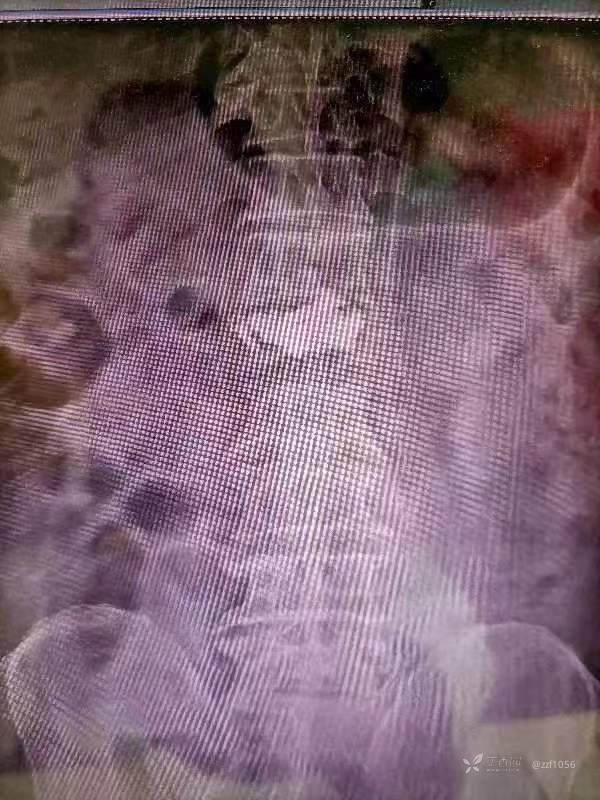

看这个病例

单侧也能打出双侧的感觉

所以说能双打尽量双打吧,毕竟马上jc了,至少不能再给相轻同行的留机会了😃